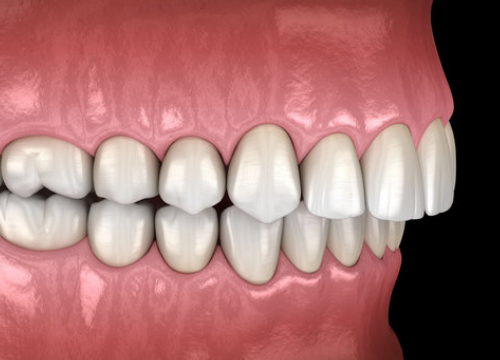

An overbite is the vertical overlap between the upper and lower front teeth when the back molars bite together. Overbites of up to 2 millimeters are considered normal and ideal. However, when there is an excessive overlap exceeding 3-4 mm, it is known as a deep bite.

Difference Between Overbite and Overjet

An overbite is often mixed up with overjet or underbite as they tend to occur together. As a general guide, an overbite is when there is a vertical overlap between the upper front teeth that cover the lower teeth from top down. An overjet is however a horizontal overlap whereby the upper front teeth protrude out and over the lower front teeth.